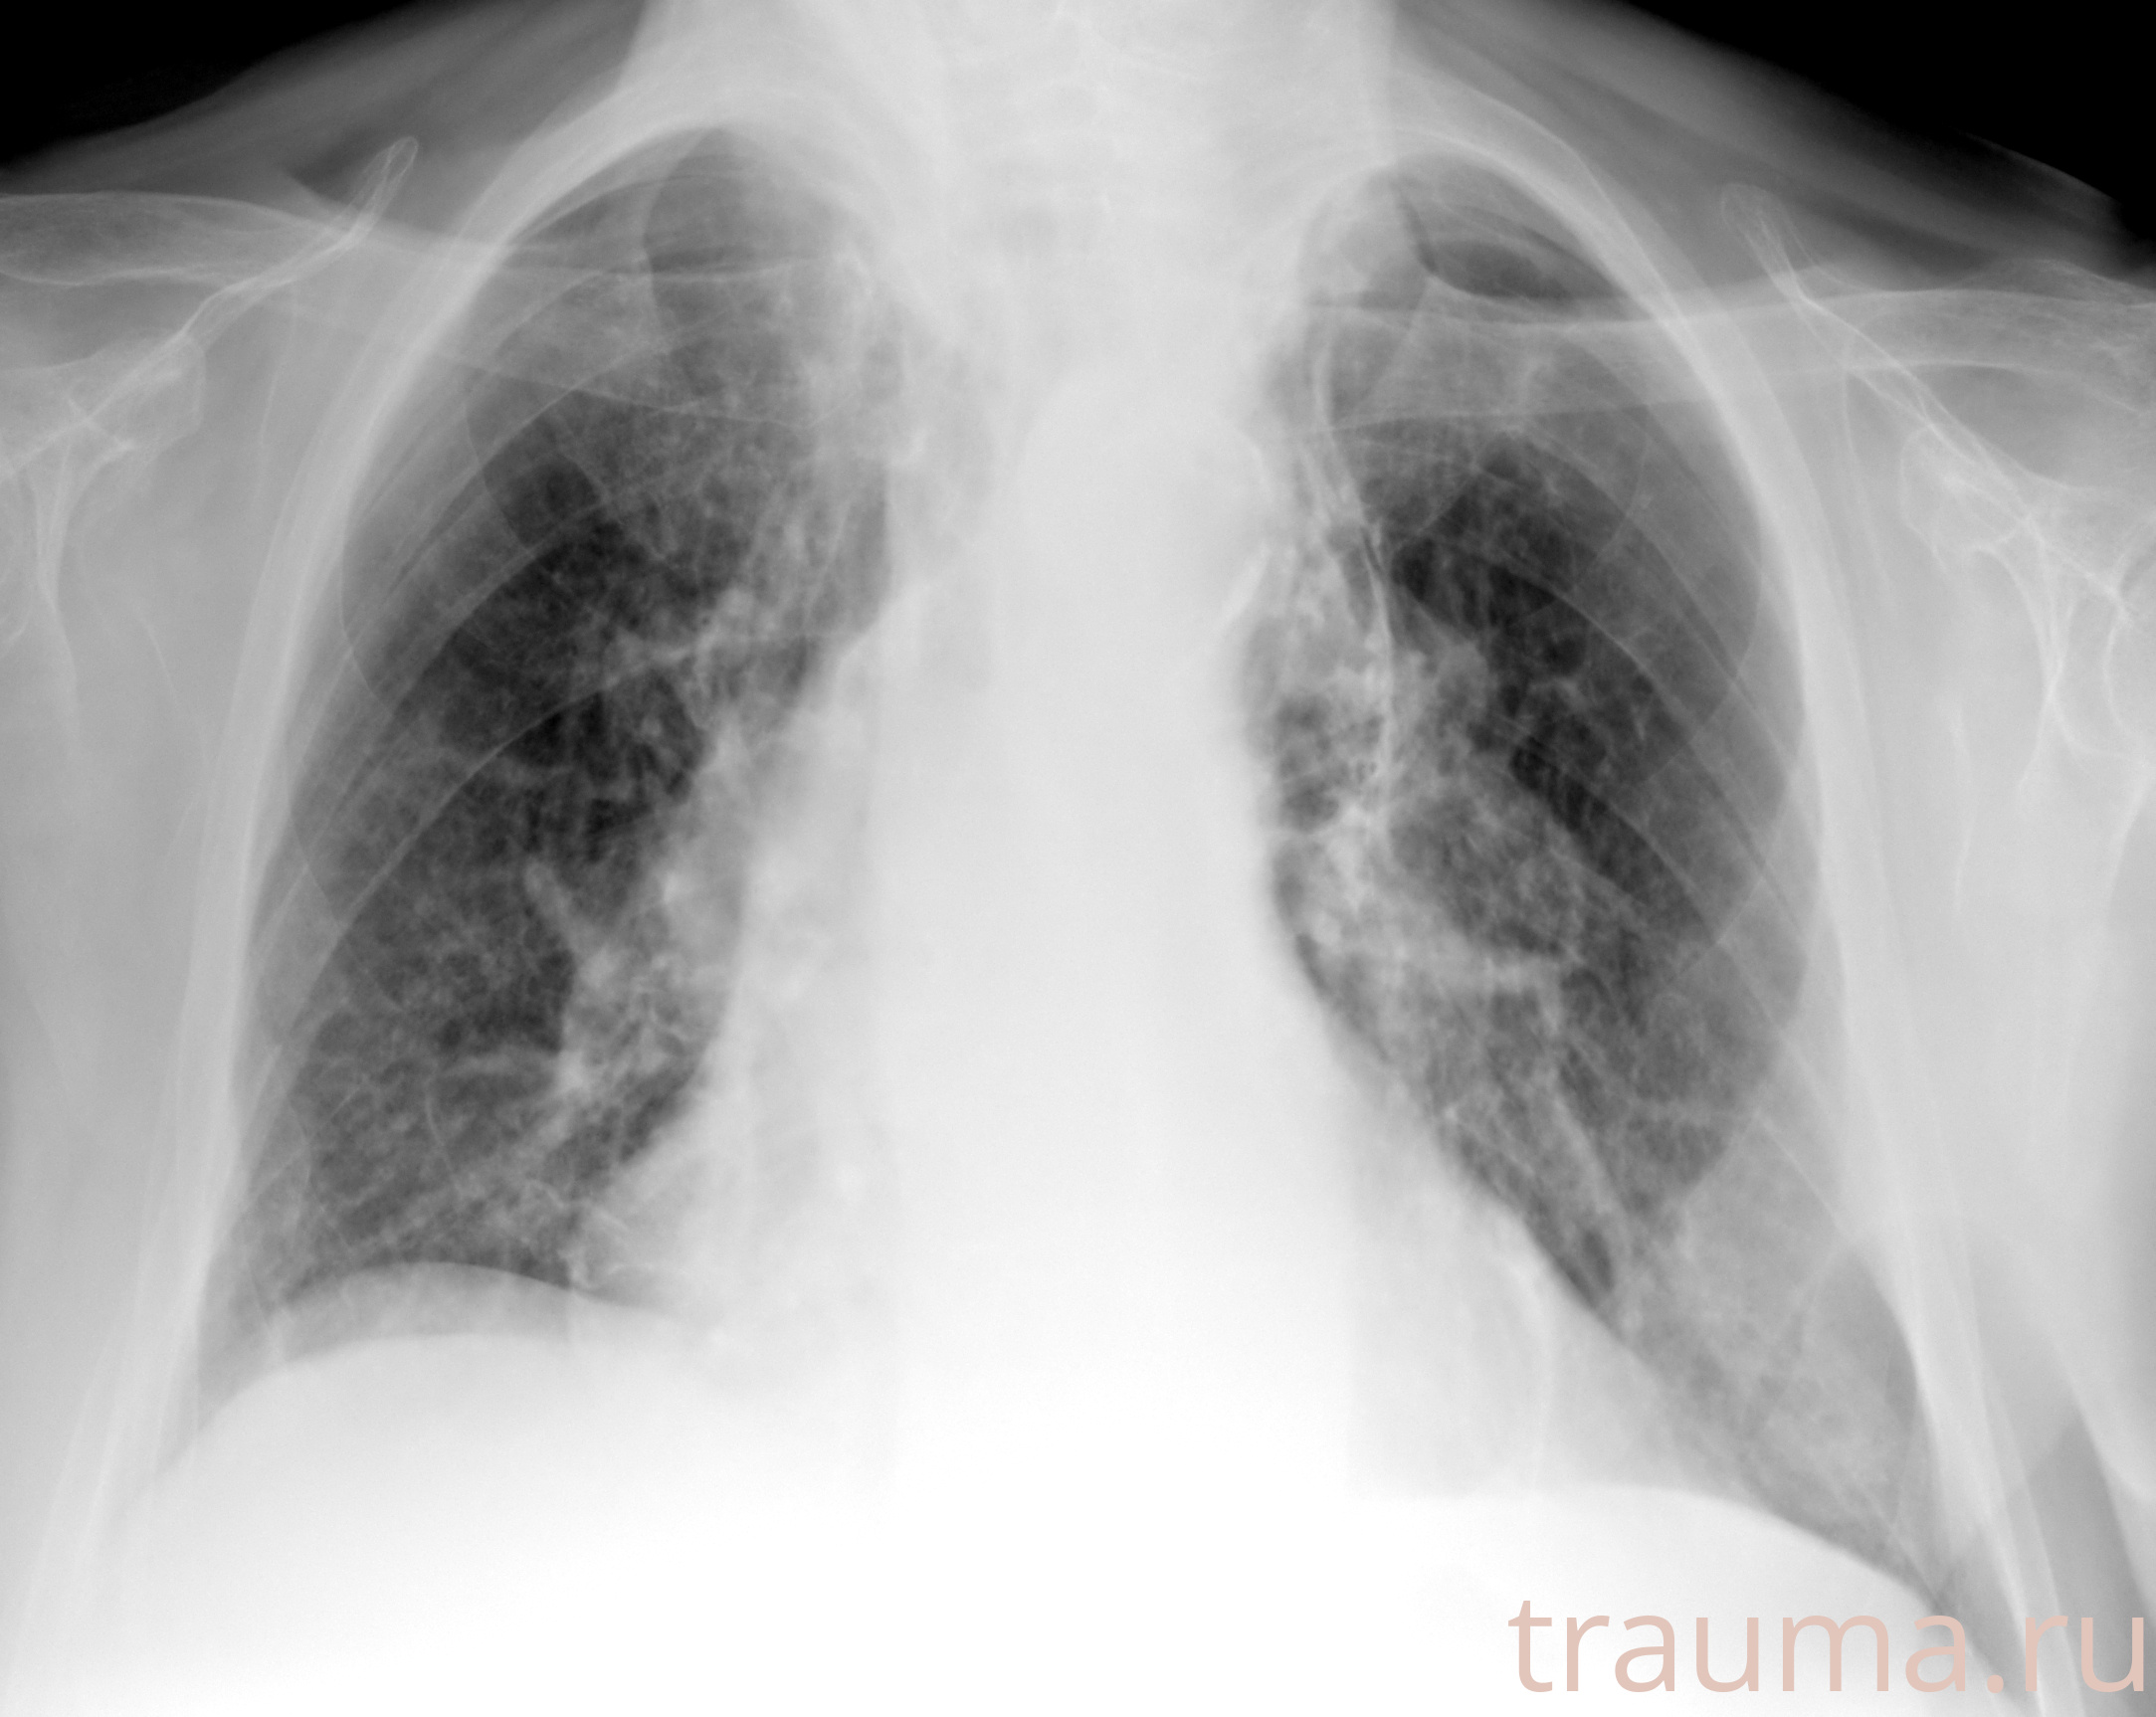

Рентгенограммы

Рентген на дому: по вашему адресу приезжает врач-рентгенолог, травматолог-ортопед с мобильным рентгеновским аппаратом, проводит диагностику травмы или заболевания, делает необходимые рентгенограммы, дает рекомендации по дальнейшему лечению. Получить качественные снимки в домашних условиях возможно благодаря уникальной методике, разработанной МосРентген Центром для института  Склифосовского

при переломе шейки бедра и пневмонии от компании МосРентген Центр - партнера Института имени Склифосовского